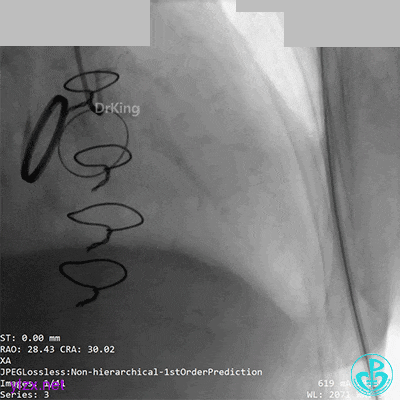

07 10天后复查造影

前降支血栓消失,回旋支恢复3级血流。回旋支夹层?血栓?

没有进一步处理。